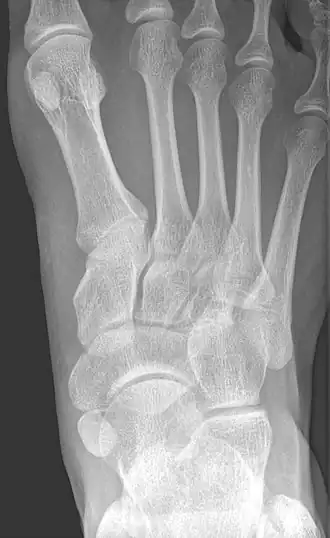

Accessory navicular bone

![]() X-ray of the foot showing an accessory navicular bone | |

An accessory navicular bone is an accessory bone of the foot that occasionally develops abnormally in front of the ankle towards the inside of the foot. This bone may be present in approximately 2-14% of the general population and is usually asymptomatic.[1][2][3] When it is symptomatic, surgery may be necessary.